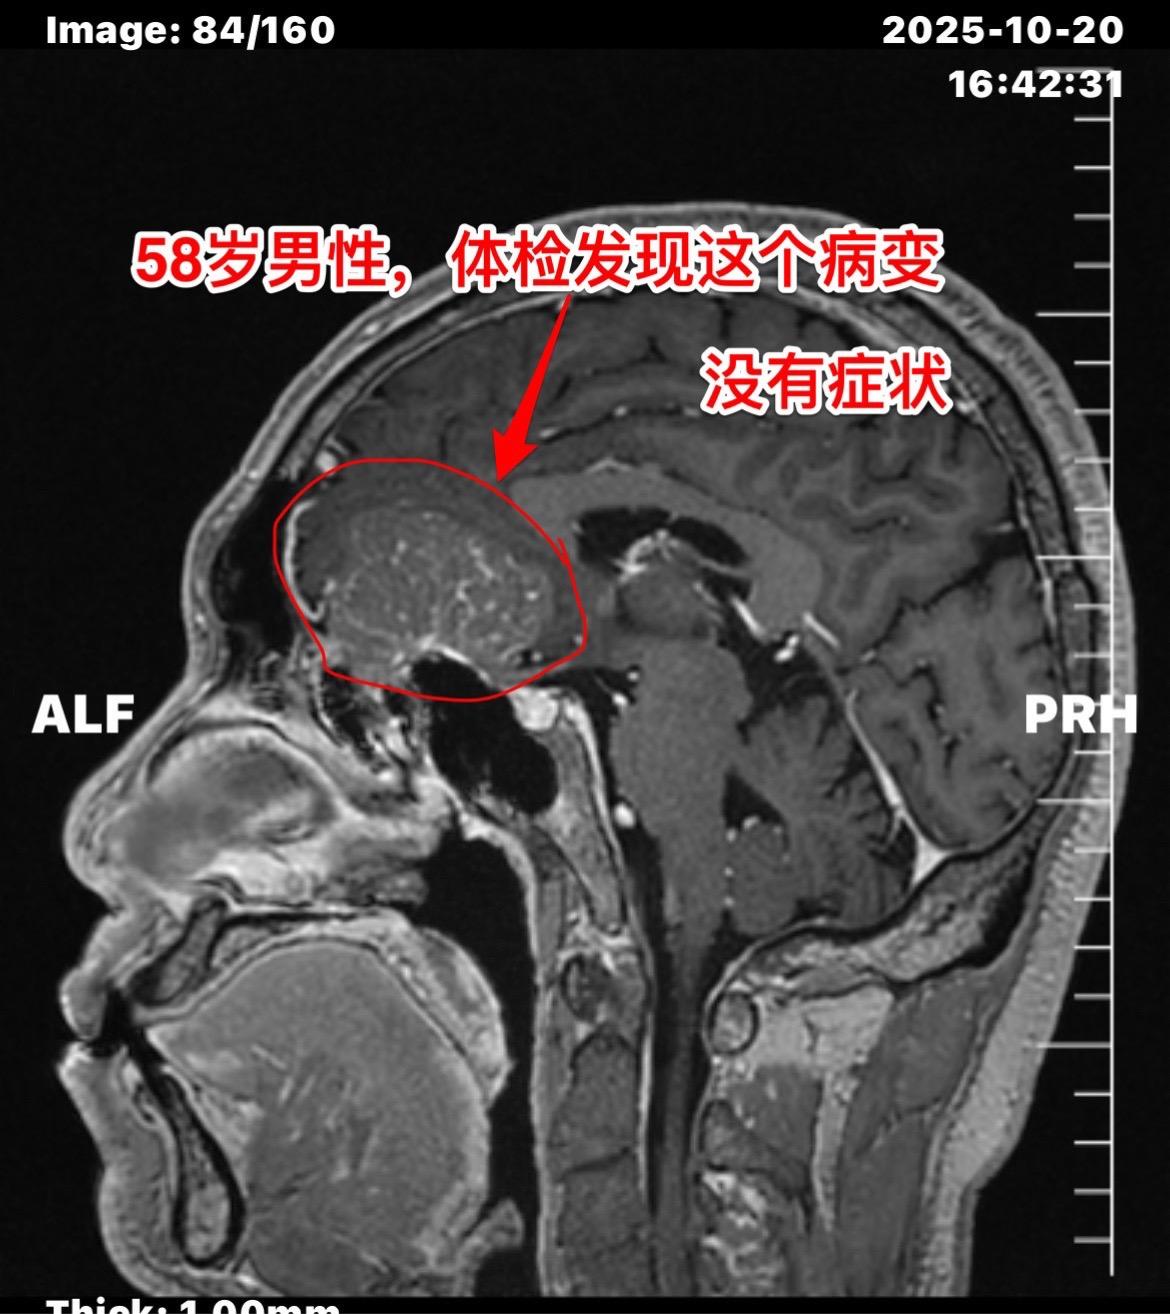

这个是脑膜瘤吗?58岁男性,洛阳市人。今年10月份单位作体检,发现这个瘤。病人无明显症状,无头痛,无视力下降。 是脑膜瘤吗? 脑膜瘤是脑部发病率最高的原发肿瘤,绝大多数脑膜瘤是良性肿瘤,不是所有的脑膜瘤都需要作手术。